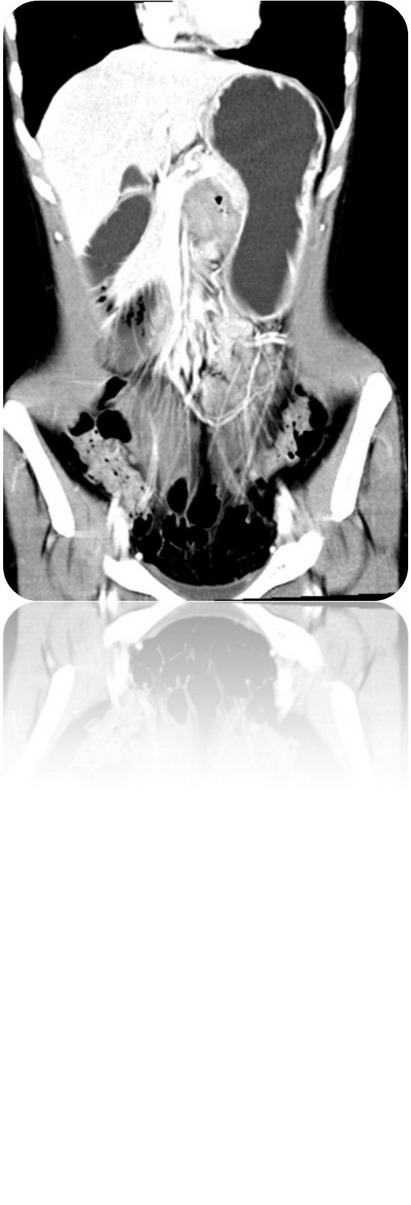

2009.6.23 腹部CT

腹膜后占位,性质待定,十二指肠局部穿透伴炎性包裹,十二指肠水平段梗阻,近端积液扩张,肝小囊肿(胰体后下方见不规则软组织密度影,大小约48mm*33mm,其内见气体密度影,增强扫描静脉期肿块明显不均匀强化,CT值约30HUPS 86HUCE,病变与十二指肠水平段、升段及胰腺分界不清,十二指肠水平段明显变窄,胃及近端十二指肠明显积液扩张。)